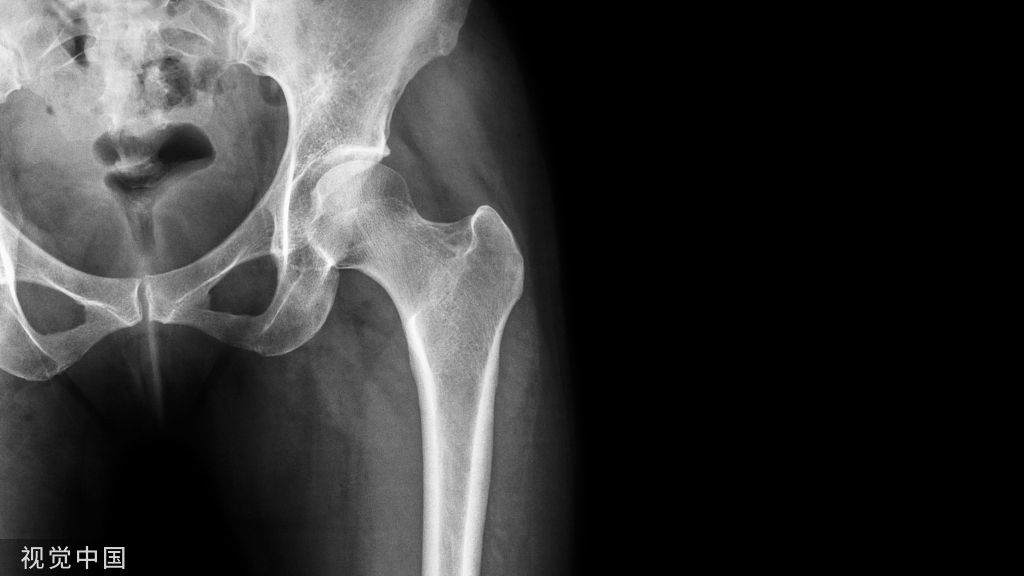

髋关节:前后位X线成像